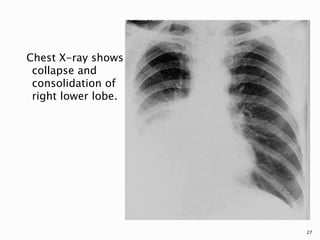

Chest X-ray shows

collapse and

consolidation of

right lower lobe.